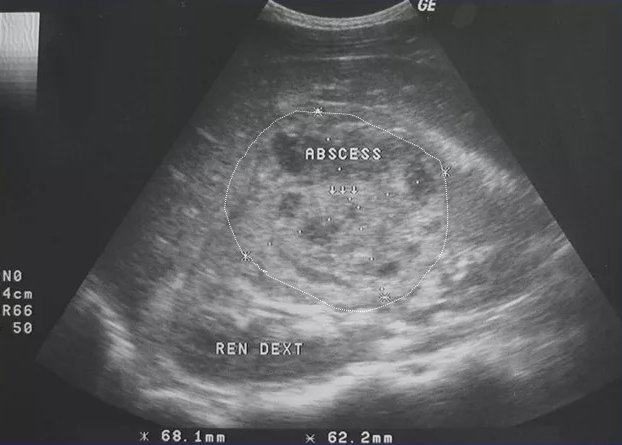

При поступлении пациенту делали УЗИ для оценки размеров полости, наличия образований, количества полостей, однородности содержимого, а также толщины капсулы и соотношения полости к полым органам и сосудам.

Результат УЗИ на 06.09.2021: правая почка (рисунок): размеры средние 12´5,6 см, положение обычное, контуры ровные, чашечно-лоханочная система не расширена, соотношение к паренхиме обычное, паренхима слегла утолщена, 1,9–2 см, без очагов деструкции, повышенной эхогенности, КМД по возрасту, отграниченных скоплений жидкости нет, однако есть «следы» жидкости в паранефральной клетчатке справа. Левая почка без особенностей.

Рис. УЗИ правой почки

Результат УЗИ № 2: правая почка: 11,3´4,3 см оттеснена вверх крупным объемным полостным образованием с неровным контуром, с неоднородным густым жидкостным содержимым, размером 15´10 см, приблизительный объем до 800 мл по типу инфицированной гематомы.